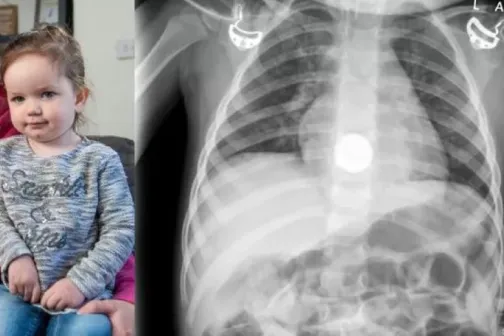

O fetiță cu necroză de esofag, salvată de medici în ultimul moment, după ce a înghițit o baterie